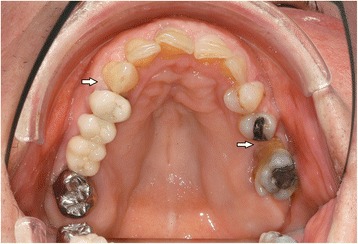

As periodontal therapy has previously failed and cyclosporine has been given since 2007 without any intraoral side-effects like gingival hyperplasia, we decided in suspicion of the recurrence of GPA with gingival hyperplasia to take a biopsy from the palatinal premolar region under local anesthesia. The biopsy was then sent for routine histopathological analysis which revealed inflammation with parakeratosis and neutrophil-granulocytic infiltration (Fig. 4). These findings were conveyed to her family doctor who decided to refer the patient to the Clinic of Internal Medicine at the University Hospital of Münster. Since the staining for c-ANCA tested positive, the recurrence of GPA was suspected. Therefore, they decided to treat the patient with rituximab via infusion. In addition to prednisolone 10 mg/day, the patient was given 375 mg/m2 rituximab weekly for a total of 4 doses. After one week of therapy, she was re-evaluated at our Department. At the follow-up visit, the patient showed complete remission of the hyperplastic gingiva (Figs. 5 and 6), the absence of pain, and the patient was able to eat without problems. Periodontal probing depths of 5 mm or more only appeared at the molars. Table 2 shows the diagnostic and treatment process of the patient in chronological order.

Fig. 5.

Resolution of the oral lesion in Fig. 1 following therapy with rituximab

Fig. 6.

Resolution of the oral lesion in Fig. 2 following therapy with rituximab